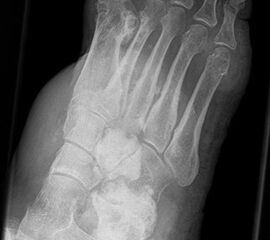

Enchondrom

Das Enchondrom ist der häufigste Knochentumor im Bereich von Hand und Fuß und nach dem Osteochondrom der zweithäufigste gutartige Knochentumor überhaupt. Die geschlechtliche Verteilung ist ausgeglichen, Enchondrome finden sich meist bei Patienten zwischen 20-40 Jahren. Dieser chondrogene Tumor verhält sich meist asymptomatisch, kann aber durch eine Knochenexpansion und Schwellung sowie Spontanfrakturen (Abb. 17) auffallen. Radiologisch zeigen sich in der Regel gut abgrenzbare Osteolysen, Matrixverkalkungen sind typisch aber nicht obligat. Die MRT zeigt typischerweise eine annähernd flüssigkeitsäquivalente Signal­qualität mit niedrigen Signalintensitäten in T1 und hoher Signalgebung in T2, die Binnen­struktur weist eine für chondrogene Tumoren typische Lobulierung mit KM-Aufnahme auf.

Im Gegensatz zu Osteochondromen ist die Lage von Enchondromen nicht auf die Metaphyse beschränkt. Sie finden sich auch im Bereich der Epi- und Diaphysen. Die kurzen tubulären Knochen der Metatarsalia und Phalangen sind bevorzugt betroffen. Hier findet sich die Läsion typischerweise im Bereich der proximalen Phalangen oder distalen Metatarsalia, eine Ausbreitung auf die gesamte Diaphyse ist von hier aus jedoch nicht ungewöhnlich. Die Möglichkeit einer malignen Entartung (Chondrosarkom) ist im Bereich der Metatarsalia und Phalangen im Vergleich zu den langen Röhrenknochen und platten Knochen extrem selten 33. Die übliche Therapie besteht in einer gründlichen Curettage. Je nach Größe des Defekts und Schwächung der Kortikalis kann die Transplantation eines stabilisierenden kortiko­spongiösen Spans notwendig werden. Zusätzliche osteosynthetische Verfahren sind nur selten erforderlich.